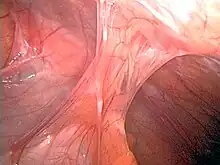

Adhesion (medicine)

Adhesions formed following appendectomy

Adhesions are fibrous bands that form between tissues and organs,[1] often as a result of injury during surgery. They may be thought of as internal scar tissue that connects tissues not normally connected.